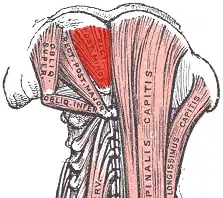

Deep muscles of the back. (rectus capitis posterior minor labeled at top center.) | |